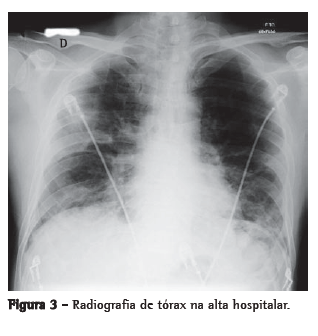

O paciente foi internado na UTI e medicado com oseltamivir, ceftriaxona, azitromicina e corticoide. Recebeu suporte ventilatório com respiração por pressão positiva intermitente, mantido com máscara de Venturi a 50% e SpO2 = 92% em repouso. Foi melhorando progressivamente, recebendo alta da UTI dez dias depois, com SpO2 = 94% em ar ambiente e melhora radiológica (Figura 3). Não apresentou febre nem instabilidade hemodinâmica durante a internação.